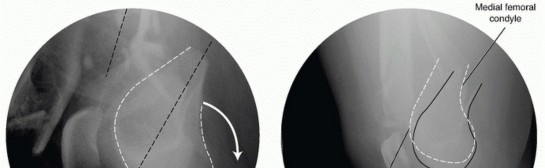

Distal femur fractures are difficult, complex injuries that can result in devastating outcomes. The distal part of the femur is considered the most distal 9 to 15 cm of the femur and can involve the articular surface. The intra-articular injury can vary from a simple split to extensive comminution. Articular involvement can lead to posttraumatic arthritis. These fractures constitute 4% to 7% of all femur fractures. If the hip is excluded, they represent nearly one-third of all femur fractures. There is a bimodal distribution defined by the mechanism of injury (see the following discussion). ## ANATOMY The supracondylar area of the femur is the zone between the femoral condyles and the metaphyseal-diaphyseal junction. The metaphyseal bone has some important structural characteristics. The predominant bone is cancellous. The cortices are especially thin. There is a wide intramedullary canal. It is also important to understand the unique bony architecture of the distal femur ( FIG 1). It is trapezoidal in shape, and hence the posterior aspect is wider than the anterior aspect. There is a gradual decrease by 25% in the width from posterior to anterior. The medial femoral condyle has a larger anterior to posterior dimension than the lateral side and extends farther distally.

FIG 1 • A. View of the distal femur showing the wider posterior aspect and trapezoidal shape. B. Lateral view of the distal femur; the shaft is in line with the anterior half of the distal femoral condyles. The shaft is in line with the anterior half of the distal femoral condyles. The normal mechanical and anatomic axes of the lower limb must be understood so that the alignment of the limb can be reestablished ( FIG 2). The mechanical femoral axis, which is from the center of the femoral head to the center of the knee, is 3 degrees off the vertical. The mechanical axis of the entire limb continues to the center of the ankle. The anatomic femoral axis differs from the mechanical femoral axis in that there is 9 degrees of valgus at the knee. This results in an anatomic femoral axis of the lateral distal femur of 81 degrees or an anatomic femoral axis of the medial distal femur of 99 degrees. The mechanical and anatomic axes of the tibia are for practical purposes identical, going from the center of the knee to the center of the ankle. The treatment of distal femur fractures can be complicated by the various muscle attachments, which can impede or hamper proper fracture reduction. The quadriceps and hamstrings result in fracture shortening; thus, excellent muscle paralysis must be obtained for proper reduction. The medial and lateral gastrocnemius results in posterior angulation and displacement of the distal segment. The distal femur “extends,” resulting in an apex posterior deformity. If an intercondylar extension is present, rotational deformities of the individual condyles can occur ( FIG 3A,B). The adductors, specifically the adductor magnus, which inserts onto the adductor tubercle of the medial femoral condyle, can lead to a varus deformity of the distal segment ( FIG 3C). 466